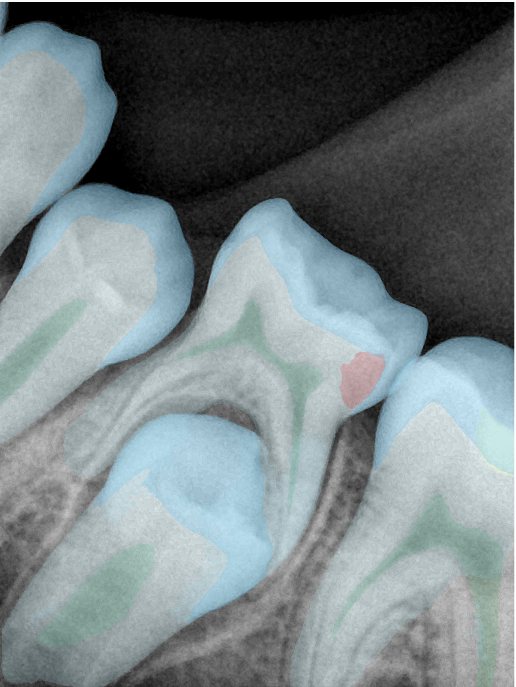

第二版算法问题测试

| 第一版 | 第二版 | 是否解决 | |

|---|---|---|---|

![]() | ![]() ![]() 边角识别有问题 龋齿识别不全 牙髓识别不全 | ![]() | 解决 |

![]() | ![]() 边角识别有问题 识别信息有误 自查(牙冠识别不全) | ![]() | 解决 |

![]() | ![]() ![]() 边角识别有误 大范围填充识别遗漏 | ![]() | 解决 |

![]() | ![]() 识别信息不全 | ![]() | 解决 |

![]() | ![]() ![]() 边角问题 牙胶识别不全 牙冠识别不全 | ![]() | 解决 |

![]() 换图片 | ![]() | ![]() 牙冠部分稍微白了一些就识别成小范围修补,部分判断异常 | 部分解决,修复类略敏感,牙冠部分稍微白了一些就识别成小范围修补,部分判断异常。 |

![]() | ![]() ![]() 牙冠识别不全 牙髓不全 根尖炎龋齿识别有误 | ![]() | 解决 |

![]() | ![]() | ![]() | 解决 |

![]() 换图片 | ![]() | ![]() | 解决 |

![]() | ![]() 牙冠识别有误 | ![]() | 解决 |

![]() 换图片 | ![]() ![]() 边角识别有误 | ![]() 修复类敏感 | 部分解决,图像过白,导致修复类判断异常。 |

![]() 换图片 | ![]() 牙冠识别不全 | ![]() 修复类敏感 | 部分解决,图像过白,导致修复类判断异常 |

结论:修复类出现了不鲁棒的情况,后续需要加入轮廓的扩充数据进行增强。